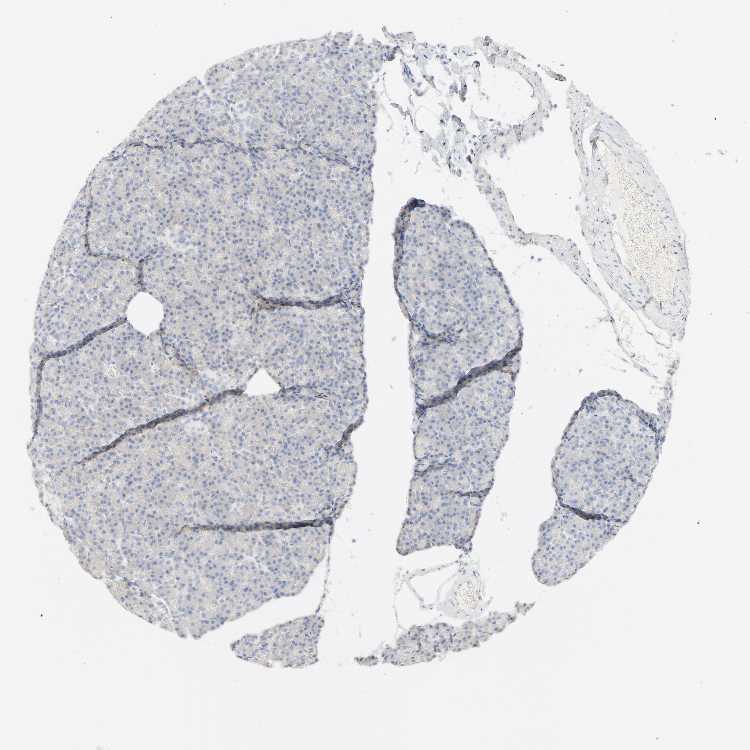

PANCREAS - Antibody stainingi

Antibody staining in the annotated cell types in the current human tissue is reported as not detected, low, medium, or high, based on conventional immunohistochemistry profiling in selected tissues. This score is based on the combination of the staining intensity and fraction of stained cells.

Each image is clickable and will lead to virtual microscopy that enables deeper exploration of all samples and also displays staining intensity scores, fraction scores and subcellular localization as well as patient and tissue information for each sample.

Antibody HPA004338

Exocrine glandular cells Not detected

Pancreatic endocrine cells Not detected